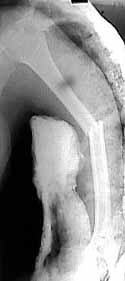

femur

humerus

tibia

The patient came to me two days after injury. Her general condition was not good with Hb 6.7 gm%. After Blood transfusions in the first stage I did standard femoral Interlocking - 10mm nail with two proximal screws. 3 days later I did Tibial and Humeral Interlocking nailing - 8mm and 6mm nail respectively with proximal locking only.

On discharge 10 days later she wass walking independently with Zimmer frame with full knee hip and shoulder movements. Xrays are attached.